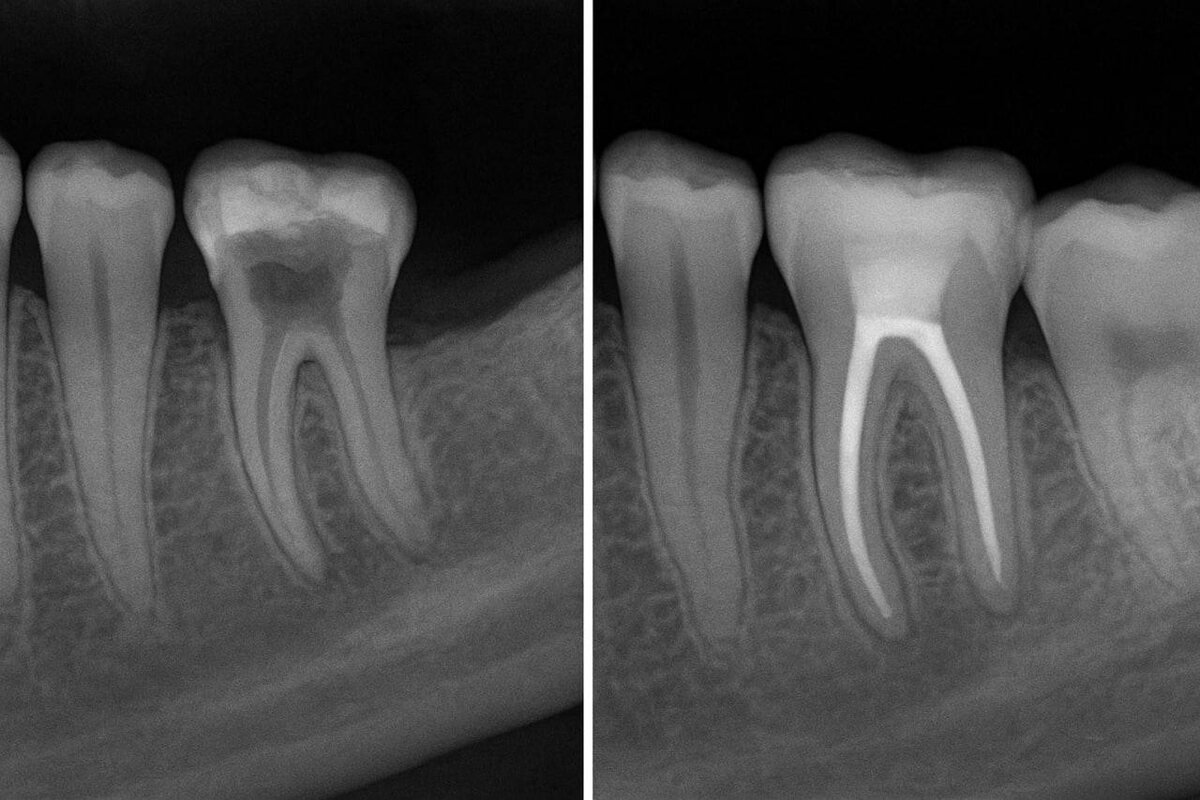

🦷 Удалять зуб или восстанавливать со штифтом? Друзья, это один из самых частых вопросов на приёме. Разбираемся 👇 ✅ Штифт ставят, если: – зуб разрушен, но корень здоров; – нужен «каркас» для коронки или вкладки; – зуб сломался, но его можно восстановить. ❌ Удаление назначают, если: – разрушен и зуб, и корень; – есть сильное воспаление или киста; – зуб расшатался из-за пародонтита; – произошёл перелом корня. ⚖️ Решение всегда принимает врач после диагностики (осмотр + снимок). И главная цель стоматолога — сохранить зуб, если это возможно. В ОМЦИП мы используем цифровую диагностику и современные методы восстановления, поэтому часто удаётся сохранить зуб даже в сложных случаях 🙌 📲 Записывайтесь к нам на консультацию — подскажем, стоит ли лечить зуб со штифтом или лучше выбрать другое решение. 📞 +79014304860 📲 @omcip_ekaterinburg 🤖 @omcip_bot

⚖️ Решение всегда принимает врач после диагностики (осмотр + снимок). И главная цель стоматолога — сохранить зуб, если это возможно.